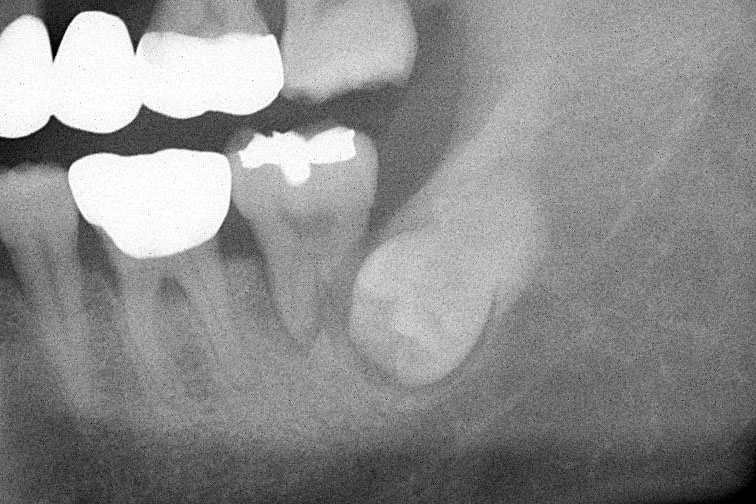

상악동 누공은 입과 코가 개통되는 증상입니다.

- 상악동 거상술이나 염증이 심한 상악의 치아를 발치하는 경우 속발성으로 상악동 누공이라는 증상이 생길수 있습니다.

- 이 증상은 구강에서 생긴 구멍이 상악동에 연결되어 막히지 않는 질환으로 물을 마시면 코로 물이 흐르는 등의 일상 생활에 상당한 불편을 초래합니다.

- 이러한 누공을 폐쇄시키는 수술은 상당한 전문적 기술과 경험을 필요로 하며 구강외과의 전문 분야로서 전문의의 진료 및 적절한 폐쇄 수술이 필요합니다.

- 누공이 적절하게 폐쇄된 이후에는 치아의 수복을 위해 치조골 이식과 임플란트 수술이 동반되는 경우가 많습니다.

상악동 누공 폐쇄 케이스

안녕하세요. 내인생치과 신창훈입니다. 이번에 소개해 드릴 환자분은 발치후 상악동이 천공 되어서 입안의 물이 코로 들어가고 코로 바람이 새는 증상이 있어서 발치한 치과에서 비흡수성 차폐막으로 막은 상태로 오셨습니다. 저희 치과에 오신 거는 발치한 날로부터 약 3주가 지난 상태로 오셨는데 발치한 치과에서는 한달이 안 되었기 때문에 더 기다려 볼 것을 권유 받…